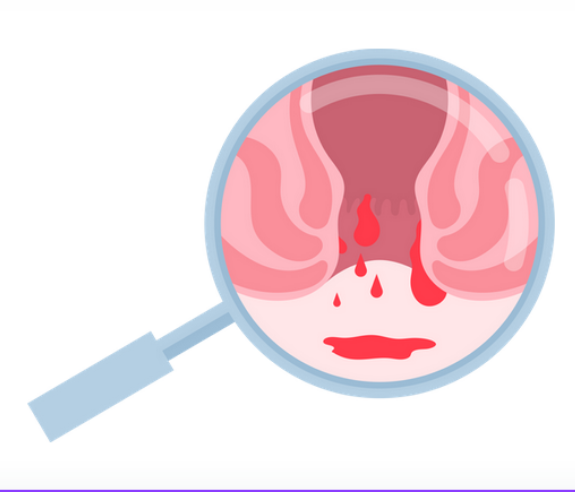

النزيف

يمكن أن يحدث نزيف خفيف أثناء التبرز، ويظهر الدم عادة على ورق التواليت

تشكل جلطة دموية

يمكن أن تتشكل جلطة دموية داخل البواسير الخارجية، مما يسبب ألمًا شديدًا وتورمًا واضحًا. هذه الحالة تعرف باسم البواسير المتخثرة